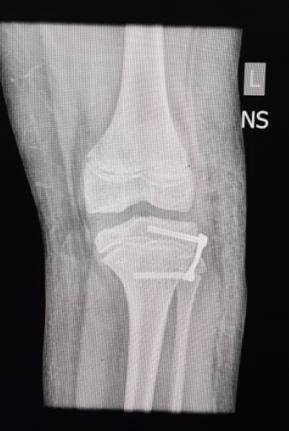

Post operative X-rays showing guided growth using 8 plates temporarily stopping growth of the outer side of proximal tibia. This would gradually correct the deformity by the inner side growing more relatively, with growth